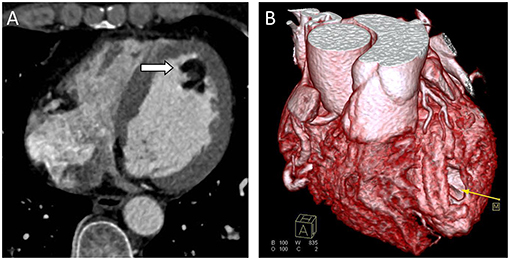

Chest radiograph showed a moderately enlarged cardiac silhouette with increased cardiothoracic ratio and no signs of pulmonary congestion. Transthoracic echocardiogram (TTE) examination showed the following characteristics: aorta 34 mm, left atrium 35 mm, LV cavity 51 mm (end-diastolic diameter), and a hyperechoic mass 30 × 27 mm located on the left side of the heart (middle-apical region), occupying almost 2/3 of the LV with blood supply from the left anterior descending (LAD) coronary artery (Figure 1). The vast mass caused a marked dilatation of the LV with mild to moderate LV outflow tract (LVOT) obstruction and decreased ventricular ejection. In addition, the apical and diaphragmatic part of the tumor was mildly calcified. CT scan of the chest confirmed a mass measuring 28 × 32 mm (Figure 2). The hyperechoic mass was highly mobile, with a peduncle measuring ~4 cm in diameter, adhering to the apical diaphragmatic surface of the LV free wall and papillary muscle.

Figure 2. Computed Tomography (CT) scans. (A) CT scan showing a well-defined hypodense tumor in the left ventricle (arrow). (B) CTA 3D reconstruction; hypodense tumor (yellow arrow).